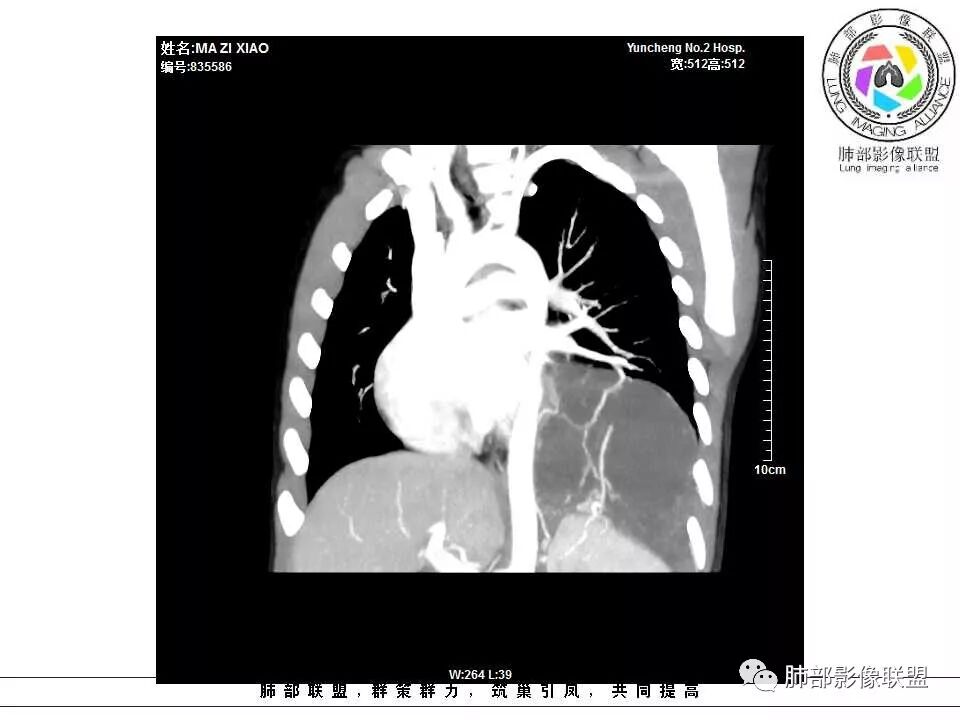

肺隔离症,供血动脉来源腹主动脉

腹主动脉供血,肺隔离症

左下肺囊状影,内有分隔,体循环供血(腹主动脉),肺静脉回流,考虑隔离症

左肺下叶多房囊性病灶,主动脉分支供血,肺静脉回流,符合肺段隔离症,应该是肺外型吧

左肺下叶占位,内部多发分割,内部可见供血血管(似来自腹主动脉分支),考虑:隔离症可能

左肺下叶囊性变,可见多发分隔,增强后分隔及边缘可见强化,并可见降主动脉分支进入,考虑叶外型肺隔离症

电话随访,患者在西安某医院手术,为肺隔离症,供血两支动脉,均来自腹主动脉,引流入肺静脉。